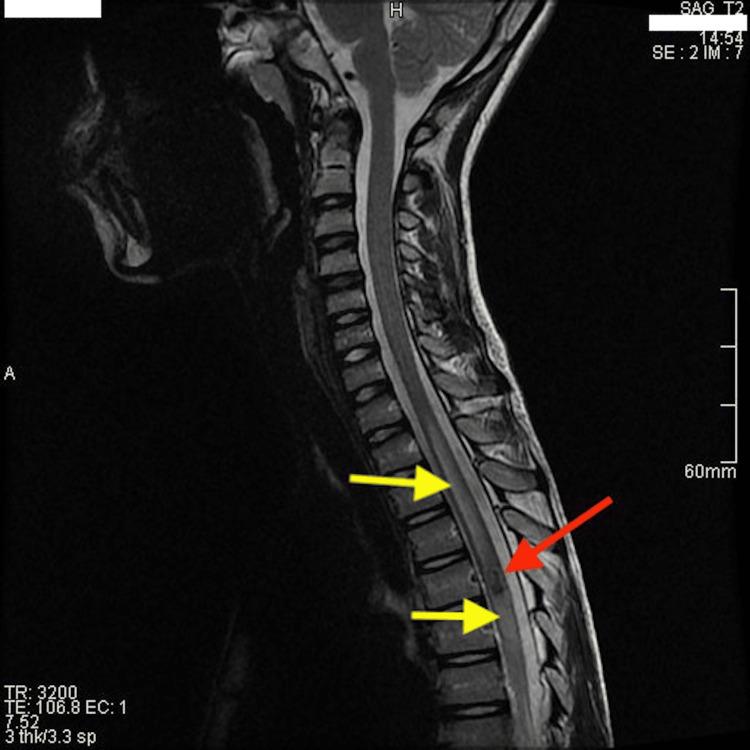

We present a case of a 13-year-old boy with abdominal pain initially misdiagnosed as gastrointestinal in origin. Despite initial outpatient management, his symptoms rapidly deteriorated, revealing a central-medullary cavernous malformation causing spinal cord compression. This case underscores the importance of a comprehensive pediatric examination and highlights new treatment approaches for spinal cavernous malformations.

我们报告一例13岁男孩,最初因腹痛被误诊为胃肠道疾病。尽管最初进行了门诊治疗,但其症状迅速恶化,结果发现是中央髓内海绵状血管畸形导致脊髓受压。该病例强调了全面儿科检查的重要性,并突出了脊髓海绵状血管畸形的新治疗方法。